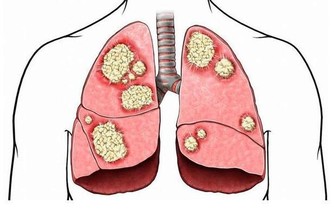

如果主子的眼皮跳逐漸加重,影響到整個眼部,那你就要注意某些疾病了,像近視、遠視、散光等眼部疾病,還有神經受到壓迫、大腦病變等原因也會引起眼皮跳哦。